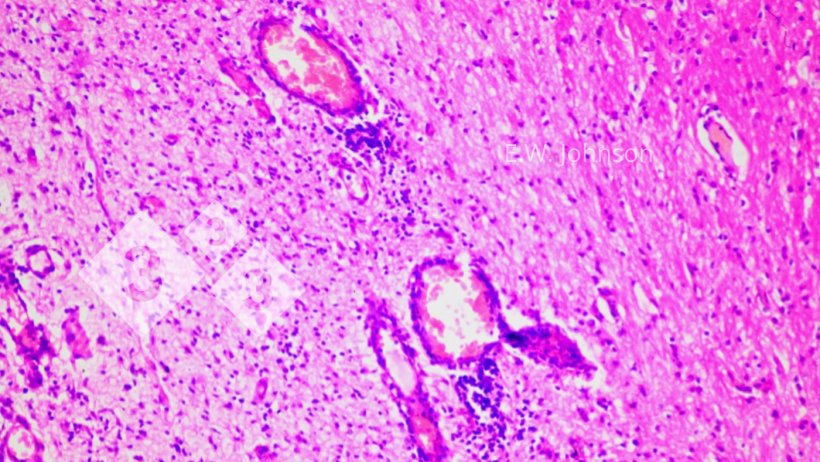

Imagen 2. Manguitos perivasculares y gliosis. Cerebro.

El examen microscópico del cerebro revela una meningoencefalitis con manguitos perivasculares y gliosis (imagen 2) e infiltración de las meninges con células inflamatorias mixtas mononucleares y polimorfonucleares (imagen 3).